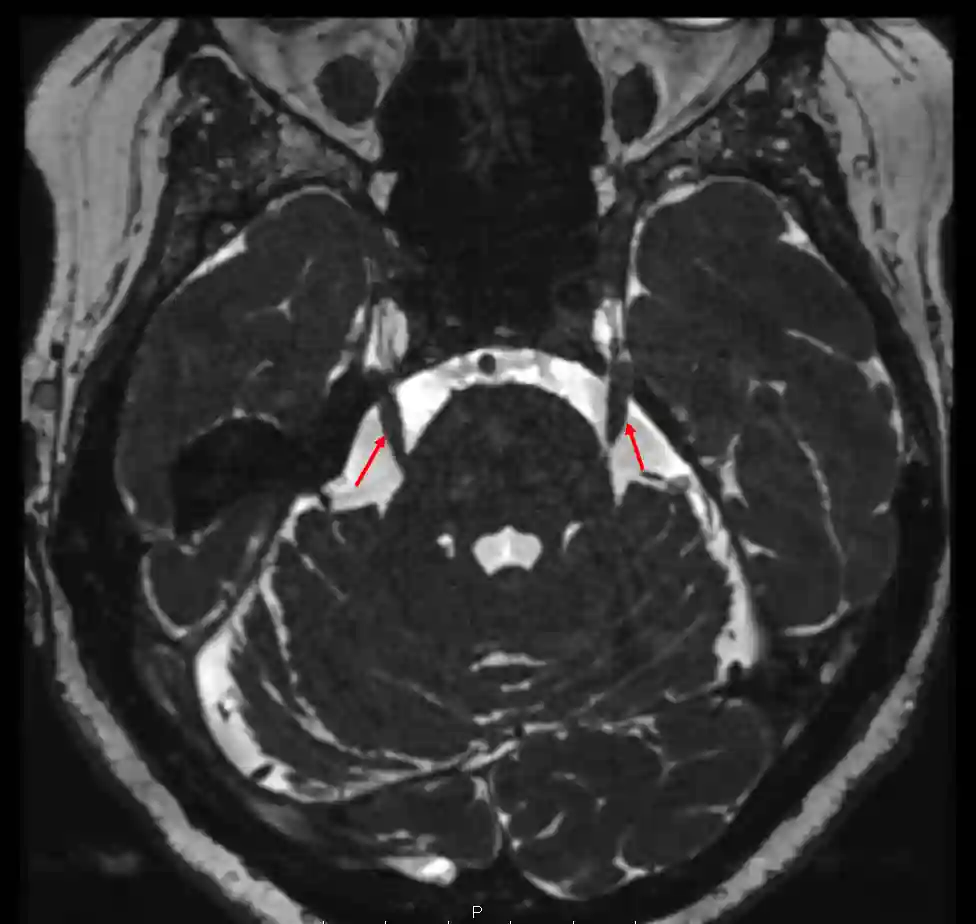

Nervus trigeminus im MRI

Darstellung des Nervus trigeminus in einer axialen CISS Sequenz im MRI.